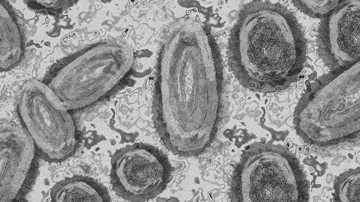

DSÖ uyardı: Afrika'da "M çiçeği" vakalarında artış yaşanıyor

Dünya Sağlık Örgütü (DSÖ), Afrika'da "M çiçeği (mpox)" vakalarında yaşanan artışa karşı uyararak bunun temel nedenlerinin belirlenmesi için yoğun araştırılmaların yapılması çağrısında bulundu.